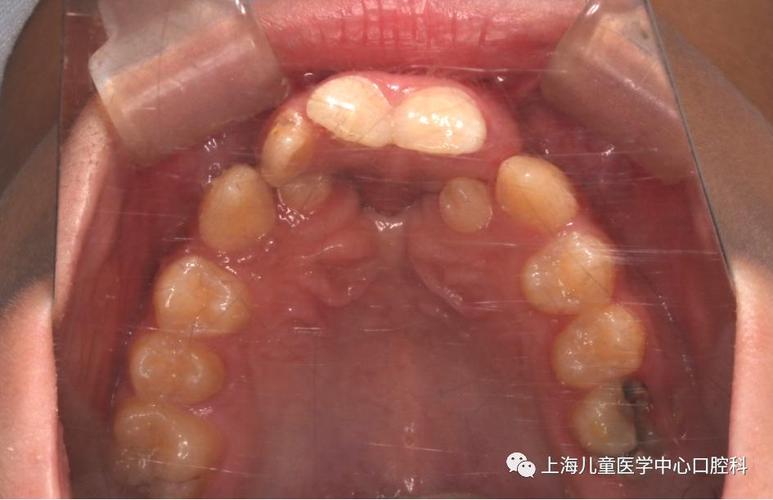

唇腭裂患者的口腔颌面特点具有复杂性,其畸形程度可分为单侧完全性唇腭裂、双侧完全性唇腭裂、不完全性唇腭裂等多种类型,不同类型的畸形表现差异较大,典型问题包括:牙弓狭窄呈“V”形,上颌骨发育不足导致面中部凹陷,牙齿萌出位置异常(如腭侧萌出、颊侧萌出),牙列拥挤或稀疏,前牙反颌(俗称“地包天”),后牙反颌及锁颌,以及因裂隙存在导致的缺牙或多生牙等,这些问题不仅影响咀嚼、发音功能,还会对患儿的心理发育造成负面影响,因此早期干预和系统性正畸治疗至关重要。

口腔正畸治疗在唇腭裂序列治疗中需分阶段进行,根据患儿不同年龄段的颌骨发育和牙齿替换特点制定个性化方案,术前正畸通常在患儿3-6个月龄时开始,主要针对完全性唇腭裂患儿,通过佩戴活动矫治器(如Hotz矫治器、Latham矫治器)将两侧裂隙的牙弓段向中线聚拢,缩小裂隙宽度,为唇裂修复术创造有利条件,同时改善牙弓形态,防止舌体压迫导致牙弓进一步狭窄,术后正畸一般在唇腭裂修复术后3-6个月开始,此时创口已愈合,主要目标为调整牙弓形态,纠正反颌、开颌等错颌畸形,促进牙弓对称性发育,对于混合牙列期患儿,重点在于管理间隙,利用缺牙间隙维持牙弓长度,引导恒牙正常萌出;恒牙列期则需通过固定矫治器(如方丝弓矫治器、直丝弓矫治器)进行全面的牙齿排齐、整平牙弓、纠正咬合关系,部分严重上颌骨发育不足的患儿需配合前方牵引等骨性矫形治疗,成年后,部分患者可能还需结合正颌外科手术,通过正畸-正颌联合治疗改善颌骨关系,达到功能与美观的统一。